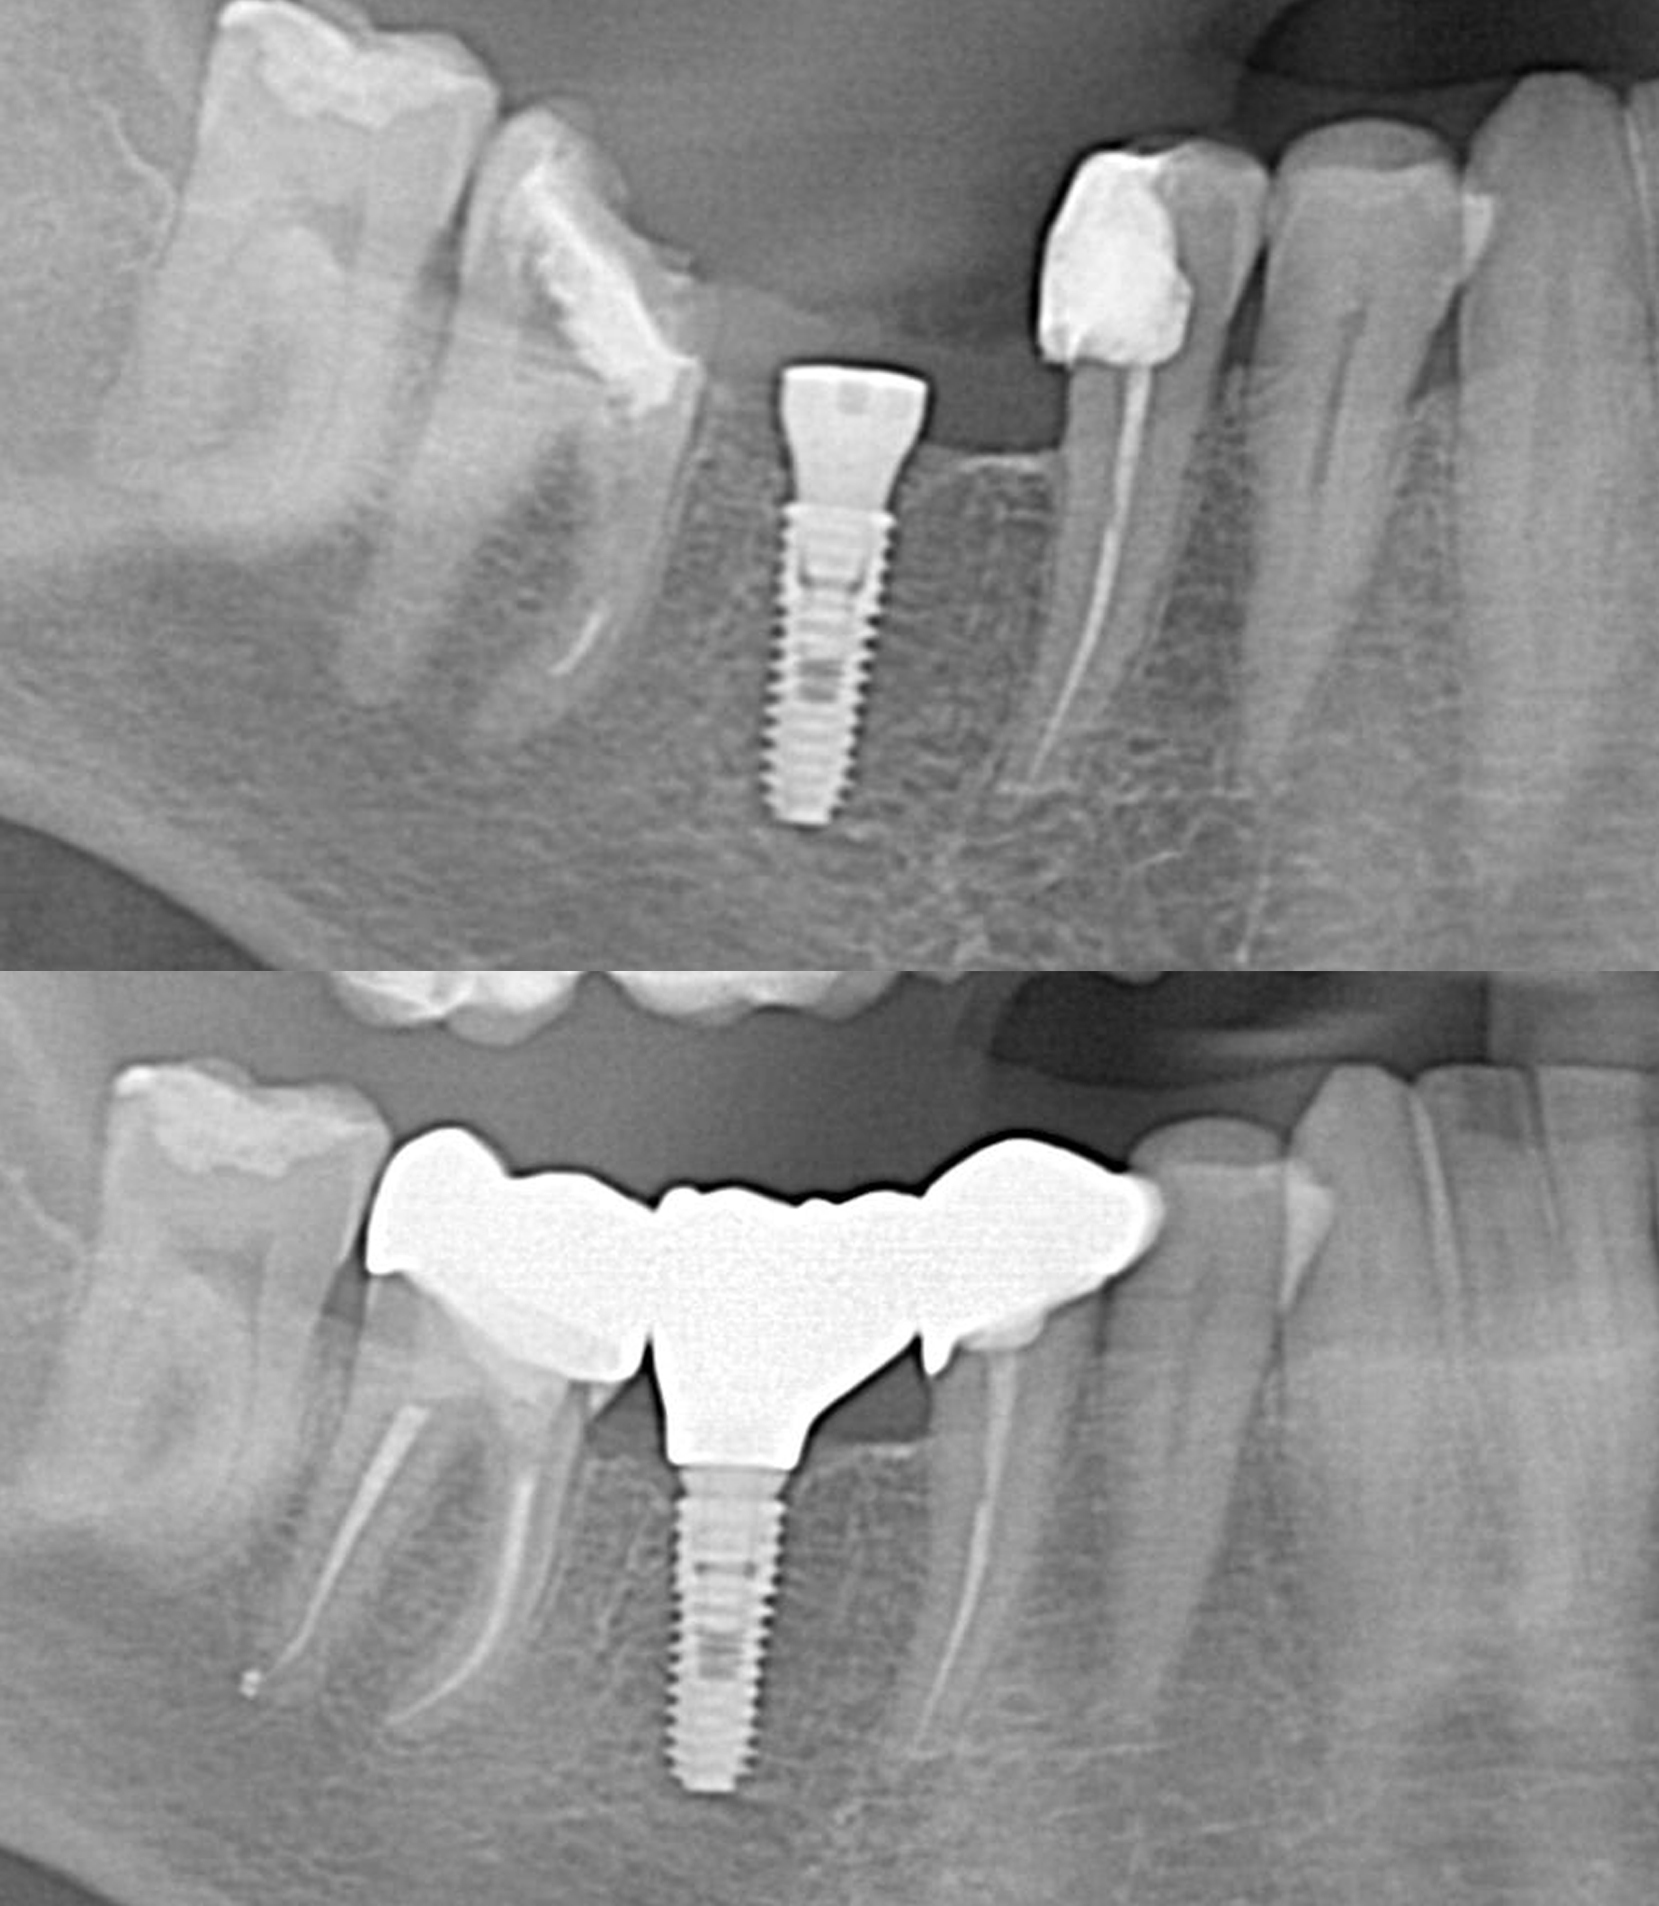

- Comprehensive Assessment: The journey begins with a thorough examination, including imaging such as X-rays or CT scans. This aids in evaluating the bone structure and determining the optimal placement for the dental implants.

- Implant Placement: Dental implants, typically made of titanium, are surgically placed into the jawbone. These implants serve as artificial tooth roots, providing a secure foundation for the bridge.

- Abutment Attachment: Once the implants are firmly integrated, abutments are attached. Abutments are connectors that link the implants to the bridge.

- Final Placement: The final step involves attaching the custom bridge to the abutments. This completes the implant bridge, restoring the aesthetics and functionality of your smile.